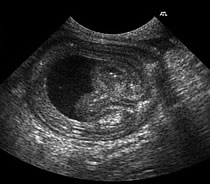

| Two examples of Intussusception |